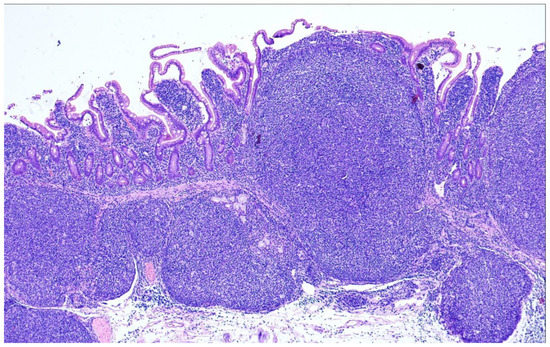

9. Duodenal-Type Follicular Lymphoma